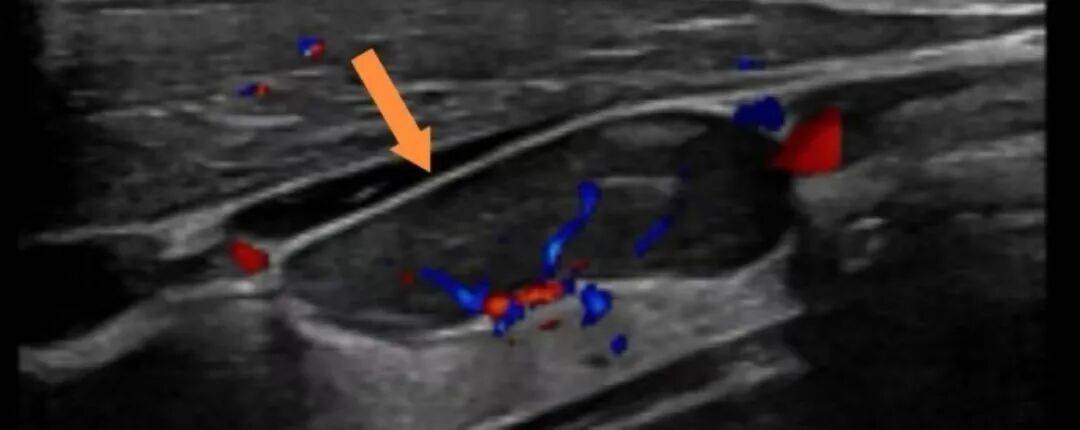

挂职期间,白熠洲曾接诊一位三阴性乳腺癌患者,新辅助化疗无效肿瘤疯长至12厘米,仔细研判后摆在面前的方案只剩下一种——手术搏一线生机。然而极度虚弱的患者与罕见的肿瘤类型,使得手术风险极高。白熠洲快速启动了乳腺癌多学科诊疗(MDT)机制,肿瘤内科、麻醉科、影像科、病理科、输血科悉数到场,团队逐项分析,针对每一个难点制定了应对措施,千方百计创造手术机会。白熠洲又请北京清华长庚医院、北京肿瘤医院专家为方案远程“把脉”。在多学科团队的守护下,患者历经休克抢救、损伤控制、改善营养状态和稳定内环境、精准手术与系统康复等一系列环节后,最终手术顺利完成。术后14天患者复诊时,体重已经增长了6kg之多。